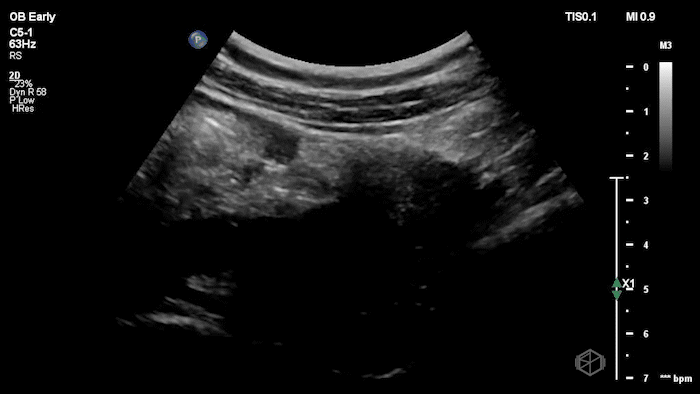

04 - What is the most likely diagnosis and definitive next step for this patient?

Left adnexal complex mass with significant free fluid concerning for ruptured ectopic pregnancy (OB Early setting).